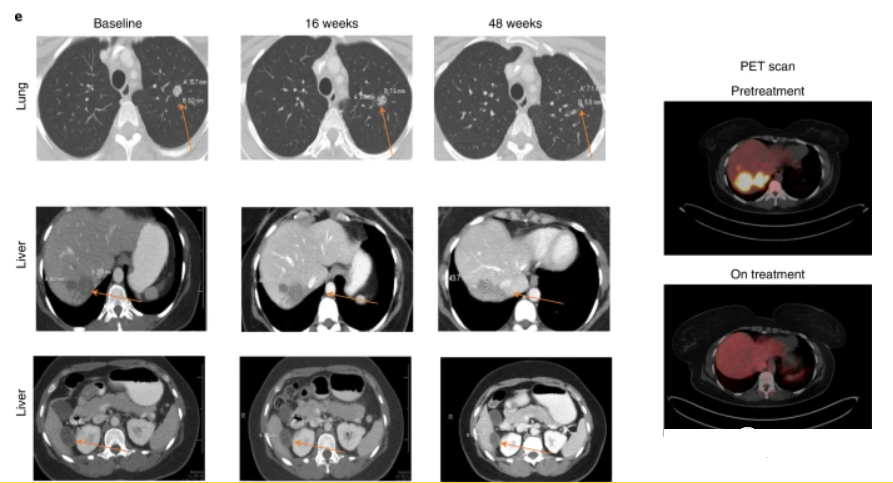

结直肠癌个体化mRNA肿瘤疫苗BNT122(Autogene Cevumeran)治疗结直肠癌患者48周后多处病灶持续缩小

个体化mRNA肿瘤疫苗BNT122(Autogene Cevumeran)治疗结直肠癌患者48周后多处病灶持续缩小几十年来,癌症疫苗已经成为免疫疗法的一种形式,通过刺激或恢复人体自身的免疫系统,来防止癌症发展或杀灭现有的肿瘤。提起mRNA技术可能更多人感觉到陌生,其实这种技术的初衷是为了研发抗癌疫苗,新冠疫苗就是在研发癌症疫苗过程中的副产品。目前,在全球至少